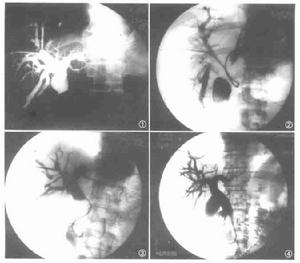

3、放射學檢查ERCP是目前診斷PSC最佳方法。經皮肝穿刺膽道造影(PTC)一般用於內鏡檢查失敗者。核磁共振膽道造影(MRCP)是一項有潛力檢查,但還需提高其成像質量。PSC特徵性的放射學表現為膽管不規則、多發局部狹窄和擴張,膽道瀰漫性狹窄伴正常擴張段形成典型的“串珠狀”改變。最近歐洲5個醫學中心對394例病人進行研究,其中73%累及肝內和肝外膽管,僅有肝內膽管改變者小於1%,僅有肝外膽管改變者為20%。有一種稱之為“小膽管”PSC,其診斷非常困難,因為受累膽管太小,以至ERCP不能顯示其異常。這種病人伴有IBD,肝功能檢驗顯示瘀膽表現;肝活檢與通常PSC相似。兒童PSC診斷比較困難,因為許多表現更象自身免疫性肝炎,在與後者鑑別時,應多做ERCP檢查,特別是伴IBD者。